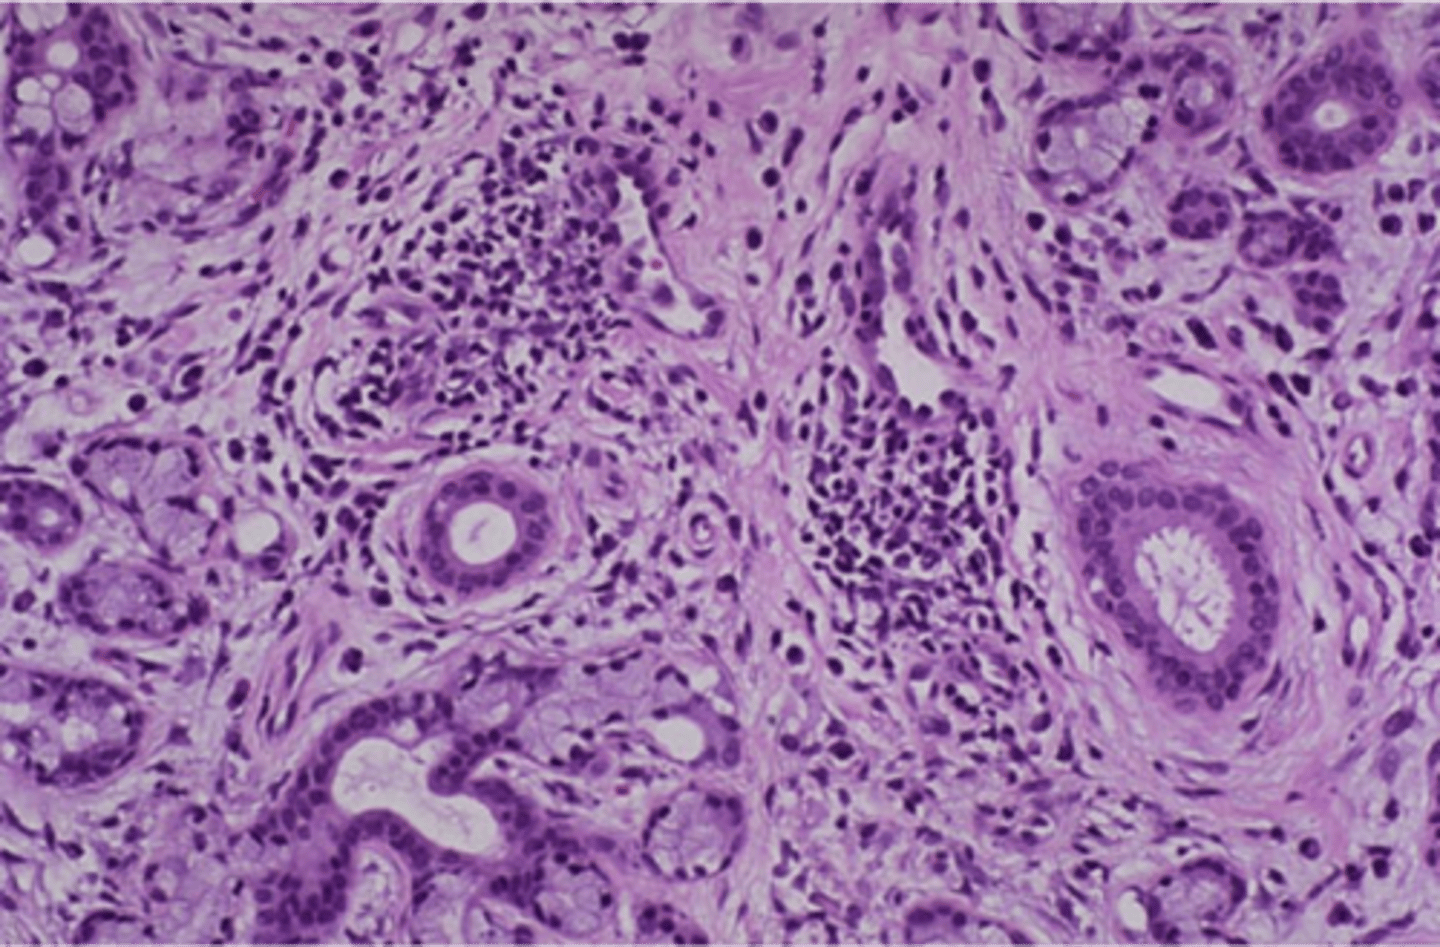

Dysphagia (esophageal webs), glossitis (beefy red tongue), iron deficiency anemia (spoon nails)

Plummer-Vinson syndrome

(may progress to esophageal squamous cell carcinoma)